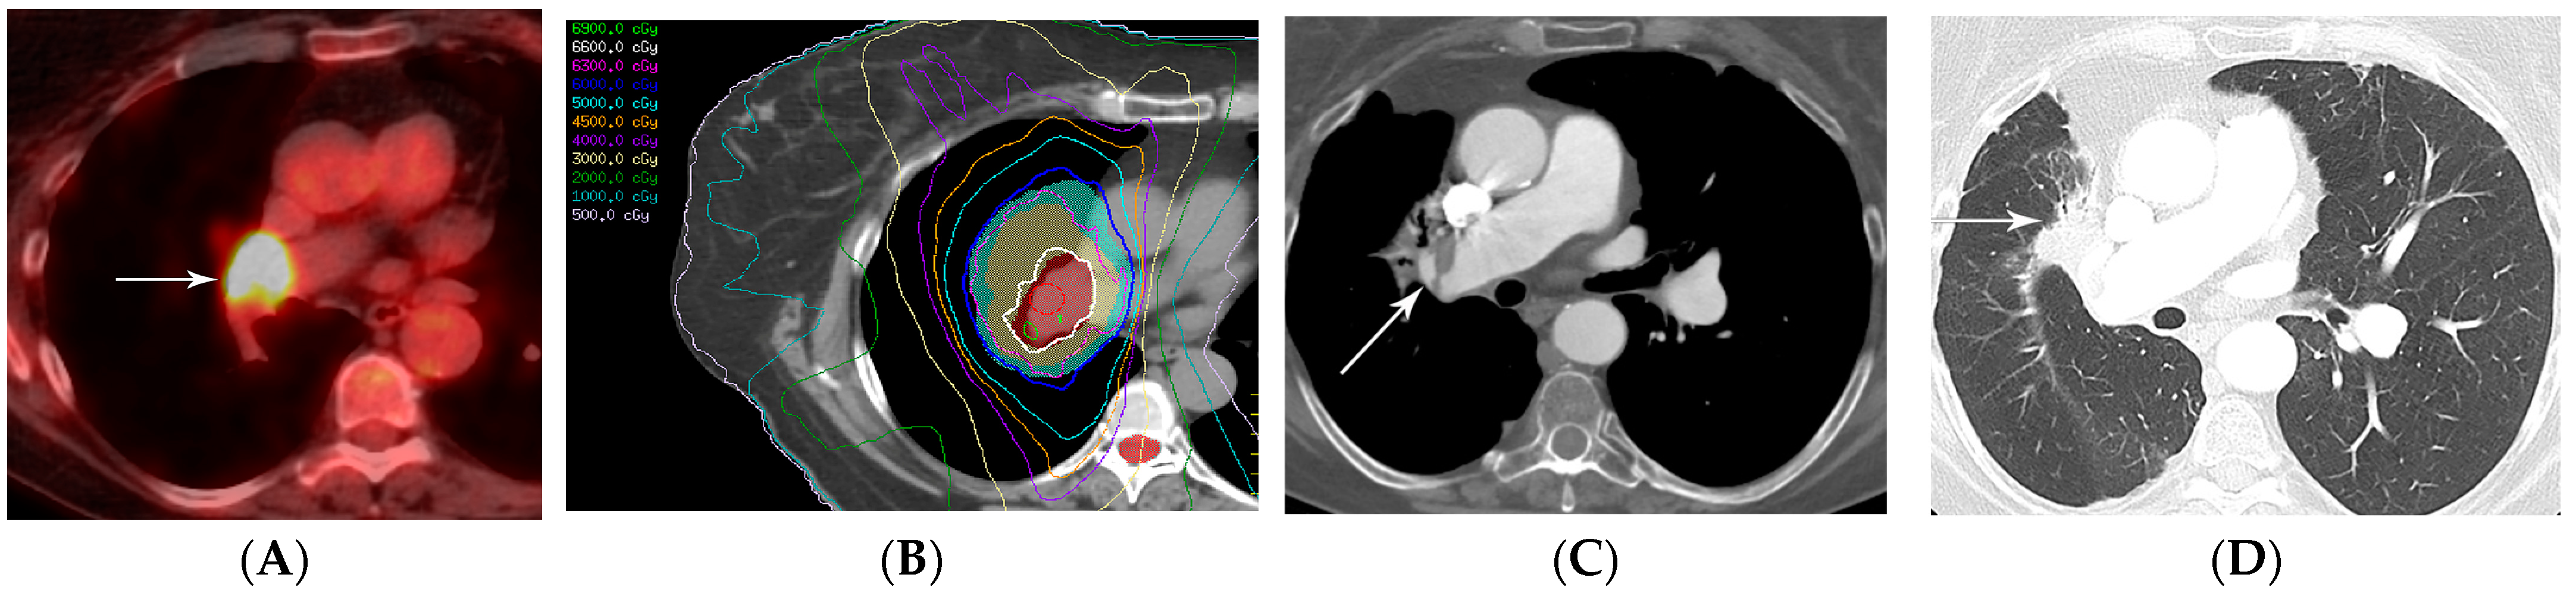

2.4. Stereotactic Body Radiotherapy

2.5. Four-Dimensional Conformal Radiotherapy

2.6. Proton Therapy